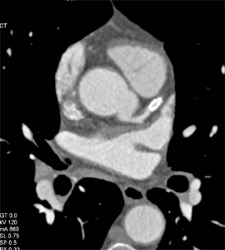

Diagnosis

Patent Bypass Graft